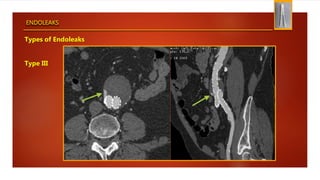

Types of Endoleaks

Type III

ENDOLEAKS